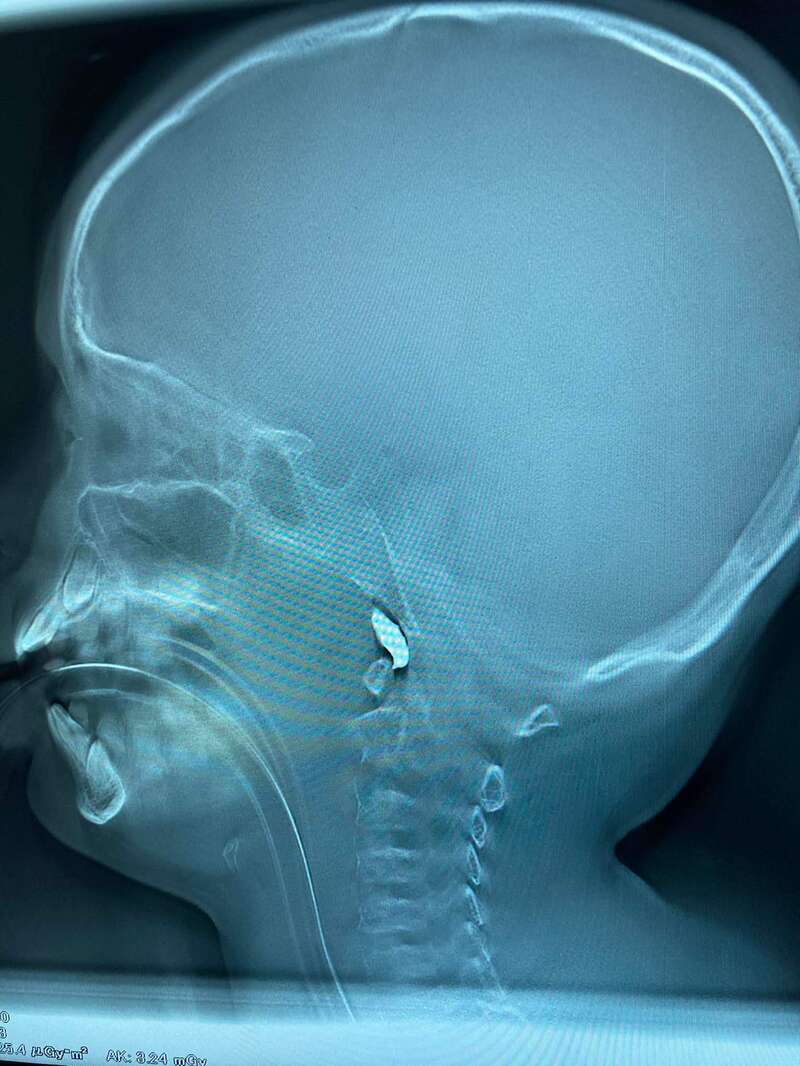

Еще один мальчик, 10 лет. Минно-взрывное. Снаряд влетел в дом… Крайне тяжелый, работаем.

В комментариях к сообщению он добавил, что осколок вошел через скулу. Локализация – очень сложная, но ключевые артерии не задело.